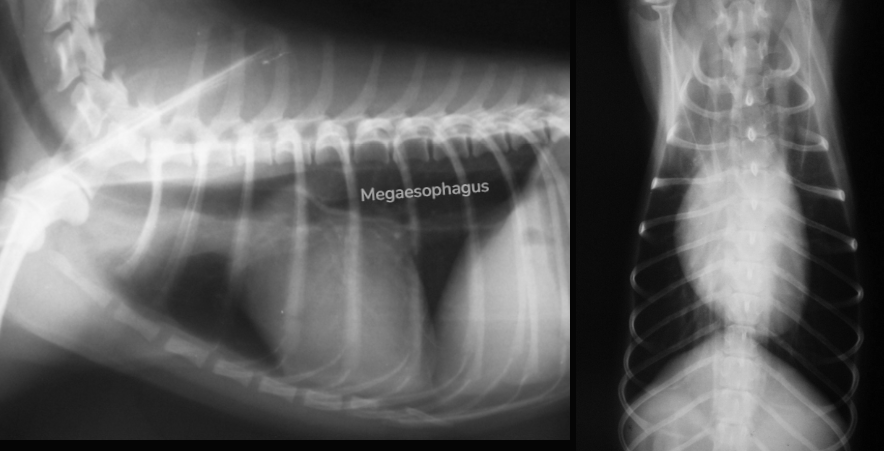

Radiographic findsings

- Megaesophagus ๊ด์ฐฐ๋จ.

- ์ธ์์ผ๋ก ์ธํด ๊ฒฝ์ถ๊ฐ ๋ฒ์ด์ง ์ ์์. C1๊ณผ C2 ์ฌ์ด๊ฐ 3mm ์ด์ ๋จ์ด์ ธ ์์ผ๋ฉด AAI (Atlantoaxial instability) โ ์ด ํ์๋ ์ด์ ์์.

- ๊ทธ ์ธ ์ฌ์ฅ, ๊ธฐ๊ด, ์ฒ์ถ, ๋์คํฌ ๋ฑ์๋ ๋ณ ์ด์ ์์.

- ํ์, ๊ฐ ์์น ์์น, ๊ทผ์ก ์์, megaesophagus

- Megaesophagus์ ์์ธ!

- MG (Myasthenia gravis) ๊ฐ์ฅ ์์ฌ. (์์ธํธ์ฝ๋ฆฐ์ด ๋ถ์กฑํ๊ฑฐ๋, ๋ถ์ง ๋ชปํ๋ ์ํ)

- ์ธ์์ผ๋ก ์ธํ ๋์์์ ๋ณด์ด๋ ๋ณ๋ ฅ์ ๊ณ ๋ คํ์ ๋, ๊ฑฐ๋์๋์ฆ์ ์์ธ์ ๋ฏธ์ฃผ์ ๊ฒฝ์ ์์์ผ ๊ฐ๋ฅ์ฑ์ด ๊ฐ์ฅ ๋์.